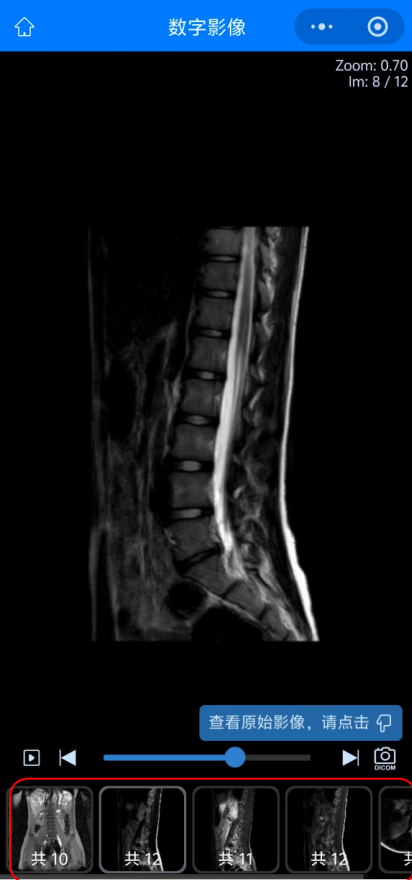

05 而點擊“查看影像”后查看到的患者的影像圖像,可以選擇下方紅色方框內(nèi)不同影像檢查或圖象處理方法來查看不同影像圖像。

09 如何進行圖像下載:首先在查看圖像功能內(nèi)點擊右下方照相機圖標,進入“查看原始影像”。